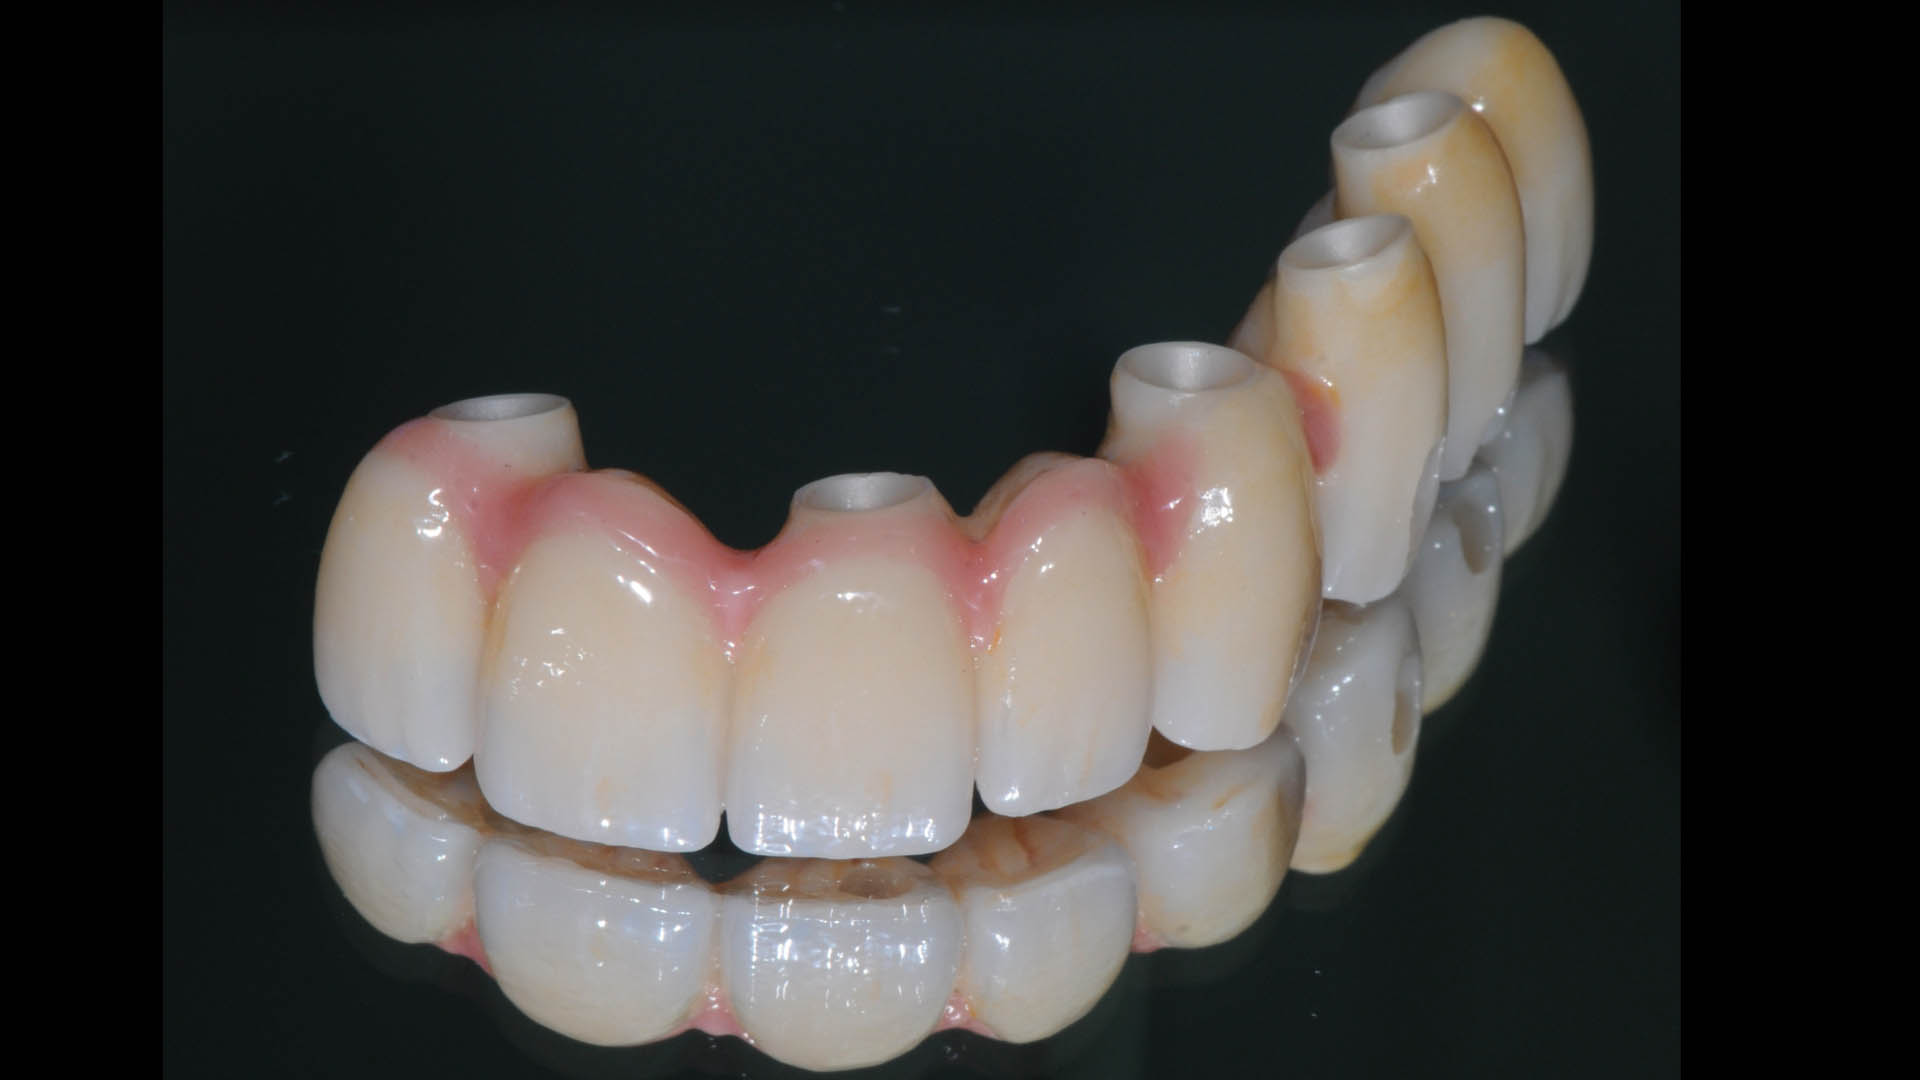

Take a glimpse into the magic of Coral Gables Dentistry through our before and after pictures. See firsthand the incredible smile makeover transformations that have brought confidence and joy to our patients.